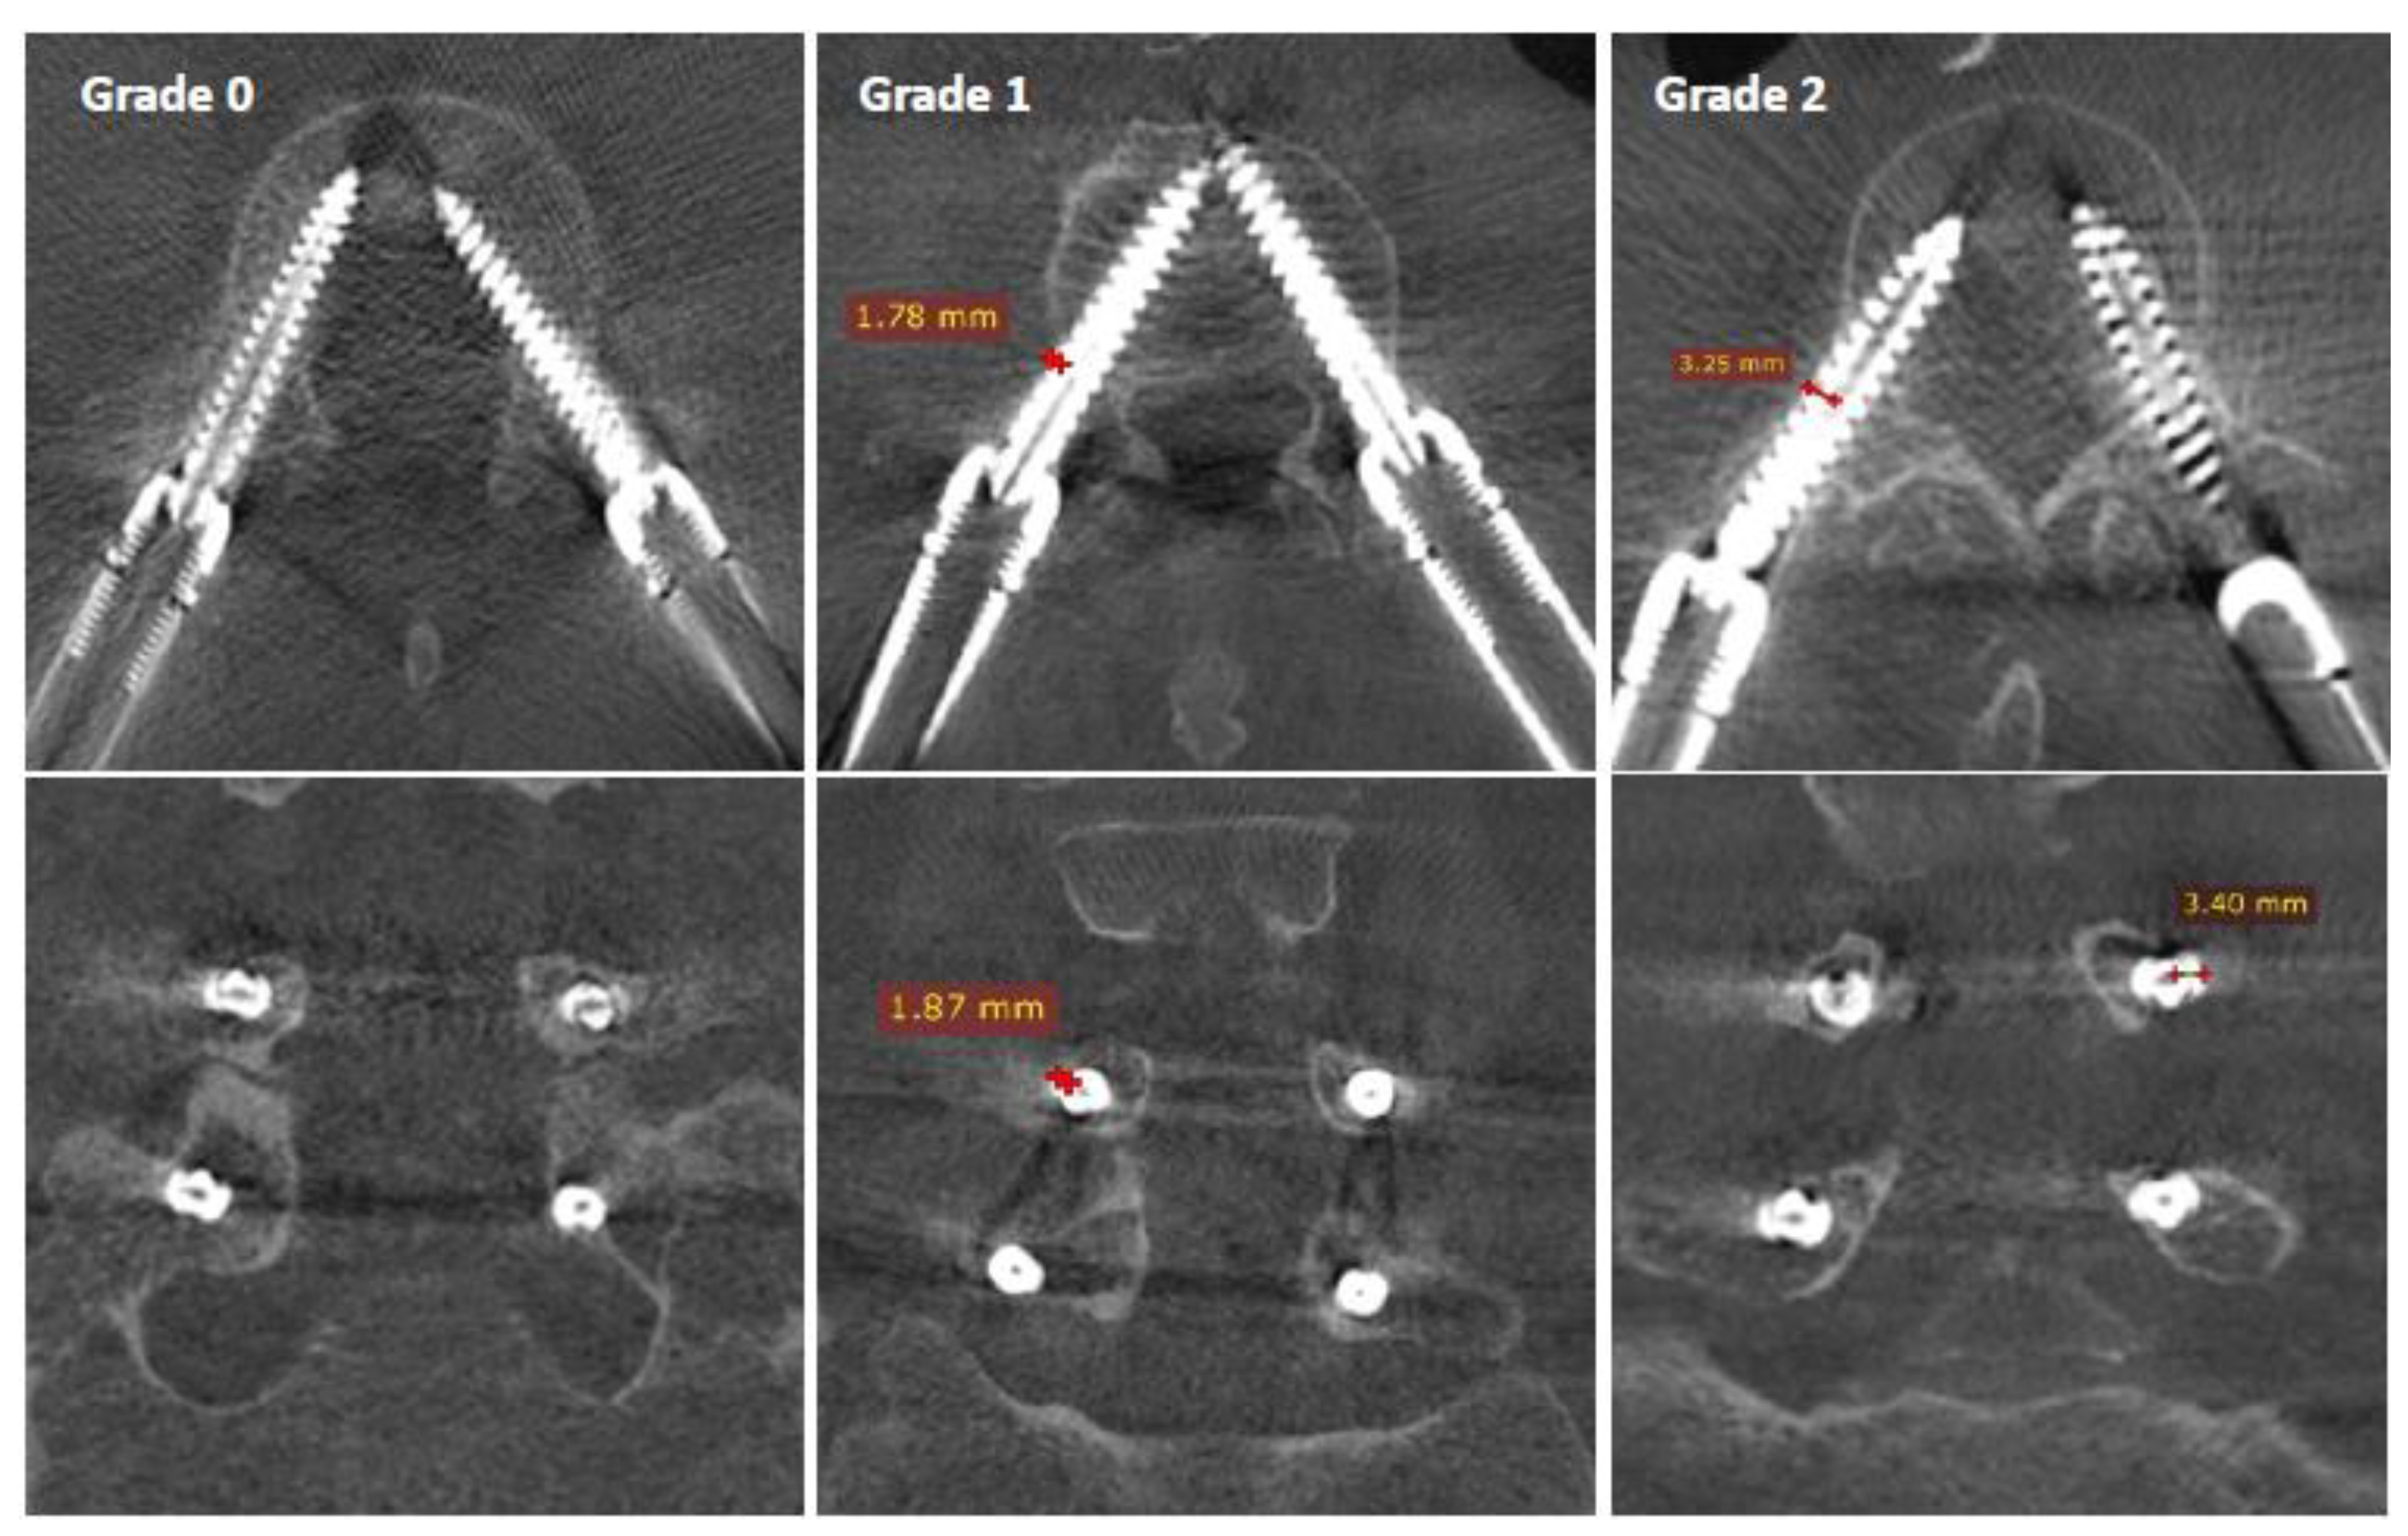

- Grade 0: screw within the pedicle without cortical breach;

- Grade 1: 0–2 mm breach, minor perforation, including cortical encroachment;

- Grade 2: 2–4 mm breach, moderate breach;

- Grade 3: >4 mm breach, severe displacement, which was not found in this cohort.